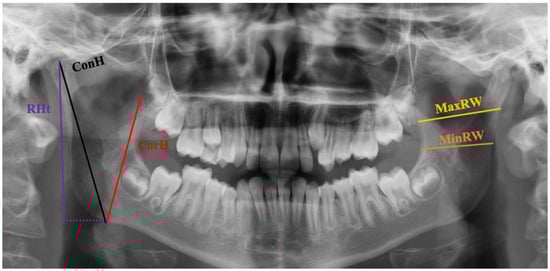

2.7. Morphometric Measurements